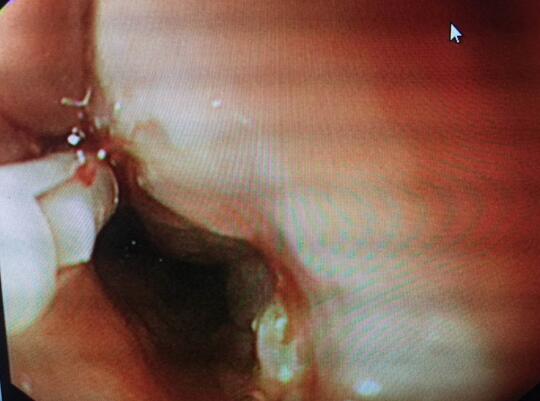

患者术后病情逐渐好转。第6天复查上消化道造影无食管龛影及造影剂无食管外漏,随后饮食从糊状流食逐渐过渡到正常,术后16天,患者饮食正常,无特殊不适,康复出院。通过本次内镜治疗,即减轻患者开胸术过程中的医源性创伤、痛苦、甚至危及生命的风险,又减轻了患者家庭的经济负担。患者及家属非常感激,多次向科室表示感谢。

钛夹完全夹闭损伤